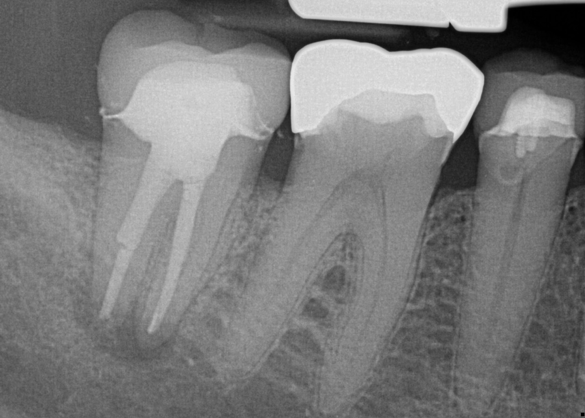

Fig 9. 33 days postoperative fiber-post placement and CAD crown.

Figure 9

The patient returned for final evaluation of the provisional calcium-hydroxide endodontic therapy and resolution of the infection (33 days postoperatively). Fistula was not present; the tooth was not sensitive to percussion or mastication. The gold crown was removed using a high-speed metal cutting bur, the remaining caries were excavated conservatively, and the endodontic therapy was completed. Placement of glass-fiber reinforced composite and composite core buildup took place. The natural tooth structure to receive the glass-fiber post and a long-term restoration was available (Figure 8). Within one appointment, the tooth was restored (Figure 9). The patient was instructed to return for clinical and radiographic evaluation after 6 to 12 months to determine progression of periodontal healing. At that time, if the healing were adequate and the tooth were stable, evaluation of the tooth would be considered every 3 to 4 years.7